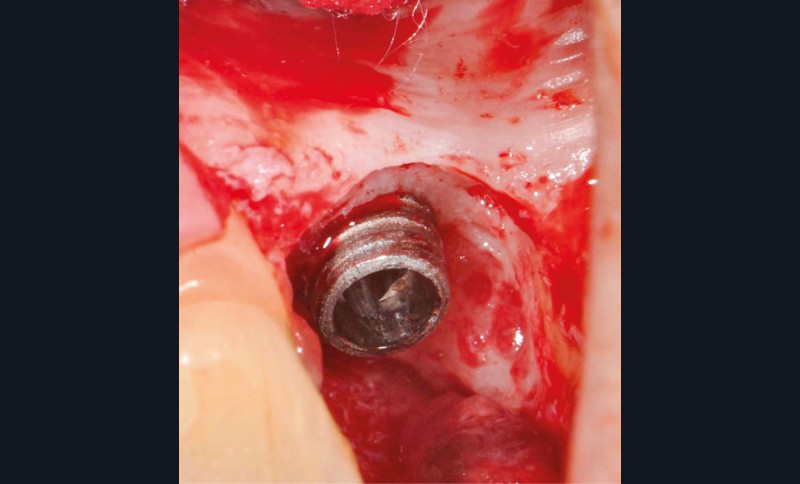

L’implant

- Posé en 2019 par son dentiste

- Couronne d’usage transvissée

- Péri-implantite diagnostiquée en 2020